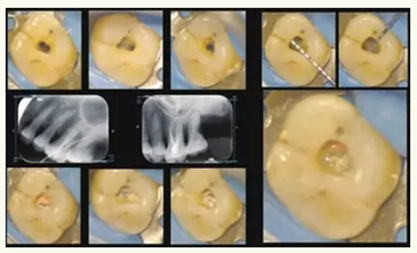

根管治療是目前牙髓病與根尖周病最有效的治療方式,所謂根管治療是在牙體表面切割獲得進(jìn)入髓腔的通道,并由此進(jìn)入牙齒內(nèi)部的根管空間,采用手術(shù)的方式清除感染病灶,并用惰性材料對(duì)根管進(jìn)行嚴(yán)密的充填以消除死腔。在國(guó)家臨床重點(diǎn)專科的建設(shè)下,牙體牙髓科建立起了顯微牙髓治療的亞專科,目前已擁有12臺(tái)根管顯微鏡,在手術(shù)放大設(shè)備的幫助下,微創(chuàng)治療已成為可能。日常治療過程中,醫(yī)師無需磨除過多的牙體組織,即可獲得牙髓治療的入路,從而保留了更多的牙體組織,使牙齒的抗力進(jìn)一步得到增強(qiáng)。

在根管顯微鏡的幫助下,醫(yī)師對(duì)于根管的解剖結(jié)構(gòu)將更為明確,顯微根管治療器械將有助于醫(yī)師更徹底的清除根管內(nèi)的感染,使根管治療成功率進(jìn)一步提高,同時(shí)對(duì)于器械分離,根管壁破壞等手術(shù)并發(fā)癥也能得到有效的控制。

▲顯微牙髓治療